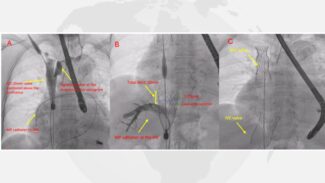

TricValve® Case: Salamanca

Performed in Spain at the University Hospital of Salamanca Dr. Javier Martín Moreiras MD, PhD Interventional Cardiologist and Associated Professor of Cardiology. University Hospital of Salamanca, Spain An 83-year-old woman with a